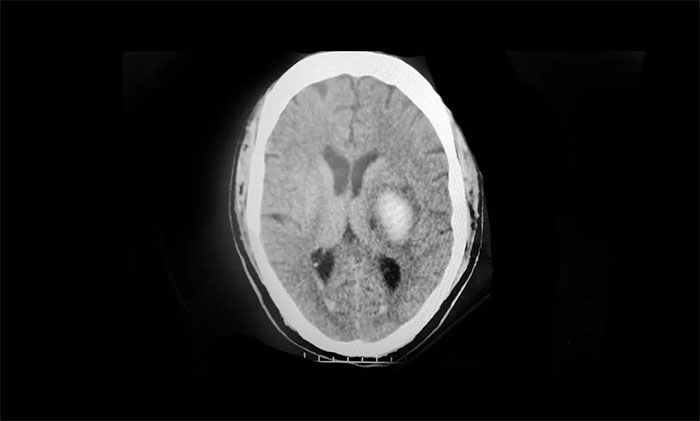

經(jīng)當(dāng)?shù)蒯t(yī)院頭顱CT 檢查提示:基底節(jié)區(qū)腦出血。立即予以脫水降顱內(nèi)壓、營(yíng)養(yǎng)神經(jīng)、補(bǔ)液、控制血壓、抗感染等對(duì)癥治療。后經(jīng)該院神經(jīng)外科會(huì)診,考慮有手術(shù)指征,建議手術(shù),但家屬當(dāng)時(shí)因顧慮手術(shù)風(fēng)險(xiǎn),拒絕了手術(shù)治療的提議。

▲ 左側(cè)基底節(jié)區(qū)出血

入院后確診為:1、基底節(jié)出血;2、高血壓2級(jí);3、Ⅱ型糖尿病;4、肺部感染。同時(shí),病程記錄陳先生有5年高血壓病史,且未規(guī)律服藥。“他平時(shí)很忙,想起來(lái)就吃,想不起來(lái)就不吃,斷斷續(xù)續(xù)的。”回憶起父親的服藥史,陳女士一臉無(wú)奈。